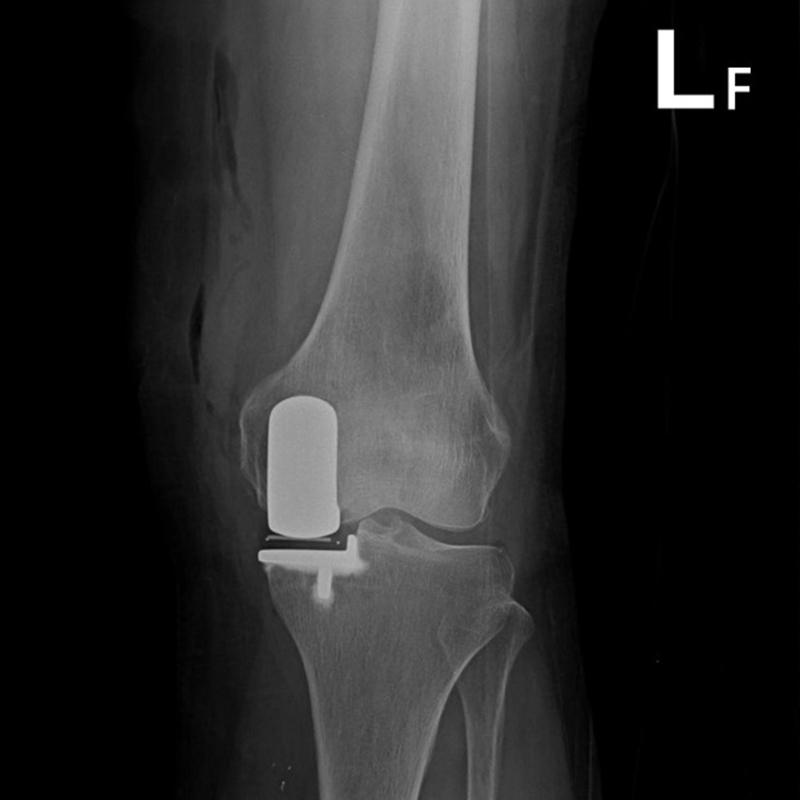

傳統部分膝置換 首頁 案例分享 膝關節手術 傳統部分膝置換 殷女士 65歲 術前 術後 張女士 71歲 術前 術後 蔡女士 74歲 術前 術後 張女士71歲 術前 術後 翁女士70歲 術前 術後 劉女士 80歲 術前 術後